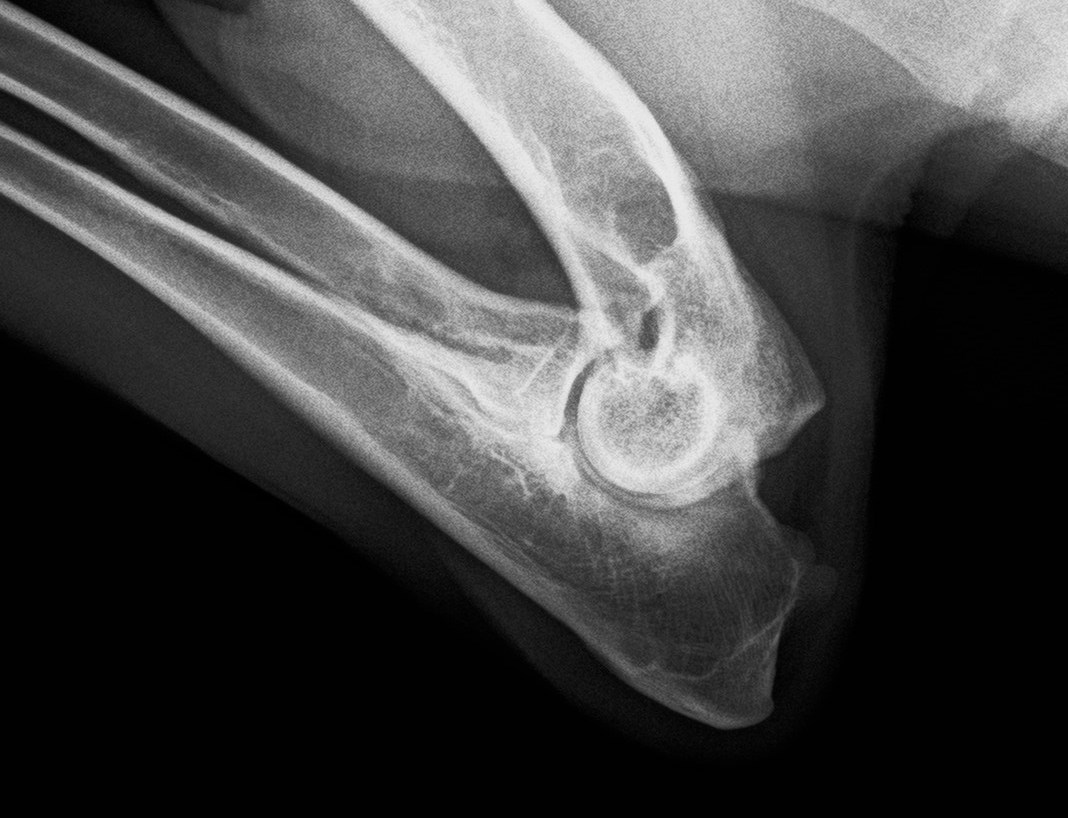

Mancata Unione del Processo Anconeo (UAP):

è la lesione provocata dal ritardo di

crescita dell’osso ulnare, il quale presenta un becco (il Processo Anconeo)

che gira dietro al condilo omerale e lo “aggancia” dando stabilità al gomito.

La sua minore lunghezza rispetto al Radio fa si che questi (in fase di

accrescimento) spinga il condilo omerale contro il Processo Anconeo non ancora

saldato nella sua cartilagine di accrescimento. Questa spinta dinamica e

continua non permette al P.A. la tranquillità necessaria per saldarsi e quindi

si ha la formazione di una pseudoartrosi o Mancata Unione. Un'alterazione concomitante che si può osservare è la curvatura del radio.

La

presenza di queste quattro lesioni principali in un gomito, porta ad artrosi

dell’articolazione, con la formazione di altre lesioni secondarie che sono

frutto della reazione del periostio al processo infiammatorio cronico. Queste

lesioni secondarie sono rappresentate da Osteofiti

che possono essere presenti sul capitello radiale o sul P.A. e dalla Sclerosi Subcondrale percepita come una

radio-opacità della parte ossea del capitello radiale ed solco trocleare

ulnare.